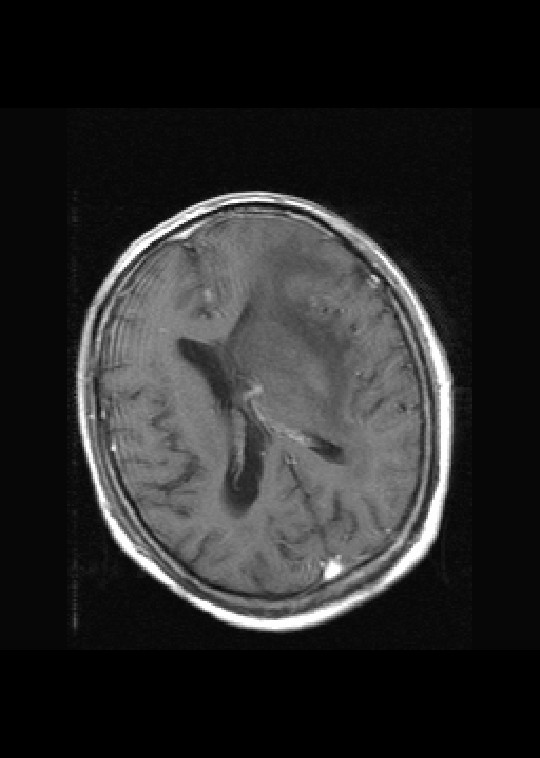

左侧基底节区病灶t1wi呈不均匀稍低信号,t2wi呈稍高信号,周围伴有水肿。增强扫描呈均匀团块样或者抱拳样明显强化,相邻的柔脑膜亦见线样强化。首先考虑淋巴瘤。可惜没有ct平扫,如果ct平扫病灶呈高密度,那么更支持pcnsl的诊断。

左侧基底节区长t1长t2异常团块状信号,增强呈明显均一强化,水肿明显,挤压侧脑室前脚,本人考虑为胶质瘤可能性大。